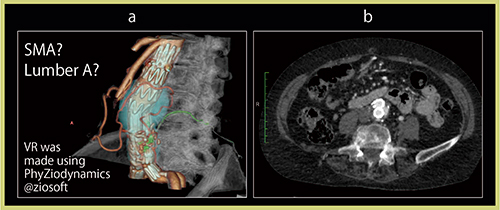

さらに,CTAはMIP画像,VR画像,アキシャル画像,DV-CTAはそれに「Ziostation2」(ザイオソフト社製)のムービーモードやcurved MPR画像を加えて放射線科医が評価し,併せてDLPと実効線量も検討した。その結果,40症例のうち5症例で,endoleakのtypeが変更となった(図1)。これは,DV-CTAで血流情報を得られるようになったからと言える。

図2は典型的なtypeⅡのendoleakで,DV-CTAでは腰動脈からendoleakに流入する血液が描出されている。curved MPR画像でも,血流の方向を確認できた(図2 b)。

図4 aのCTAのアキシャル画像では,endoleakに2本の腰動脈(→)がつながっているように見え,一見typeⅡと診断してしまう。しかし,その後,瘤径が拡大したためDV-CTAを施行したところ,ステントグラフトの下側の圧着が不十分で,そこから血流がsacに向かっているのが描出され,endoleakから2本の腰動脈へと

流出していた(図4 b)。このことから,typeⅠbのendoleakと診断された。typeⅡであれば腰動脈に塞栓術を施行するが,typeⅠbでは再度ステントグラフトを圧着するか,ステントを追加することになる。このように,type分類が正確にできることで,確実な治療が可能となる。

図4 TypeⅠb endoleak症例

a:CTAアキシャル画像 b:DV-CTA画像